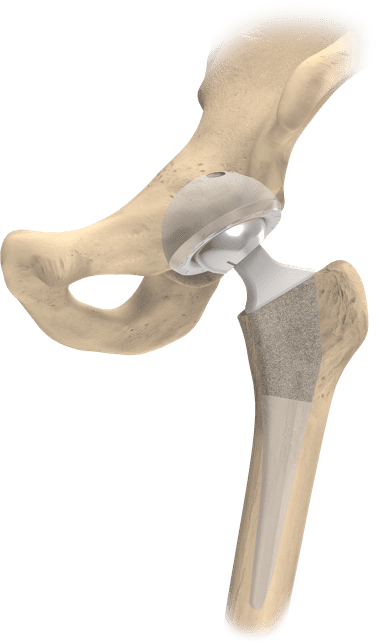

Acetabular Component

Femoral Head

Acetabular Liner

Femoral Stem

Before considering a total hip replacement surgery, many patients may go through a continuum of conservative care starting with rest of the hip, lifestyle modifications, pain and anti-inflammatory medications, and/or physical therapy. For those who fail conservative treatment because the cartilage in the hip is too worn or there is damage to the bone surface, your physician may recommend total hip replacement surgery, also known as hip arthroplasty, to alleviate the pain and get you back to living life.

Hip replacement surgery is the second most common joint replacement surgical procedure 2. In a total hip replacement surgery, the surgeon removes the femoral head on top of the proximal femur and the damaged cartilage in the acetabulum. After these areas are removed, the surgeon replaces them with medical implants that replicate the hip joint so that the new artificial joint is designed to perform the motion and function of the natural hip without pain or compromise.